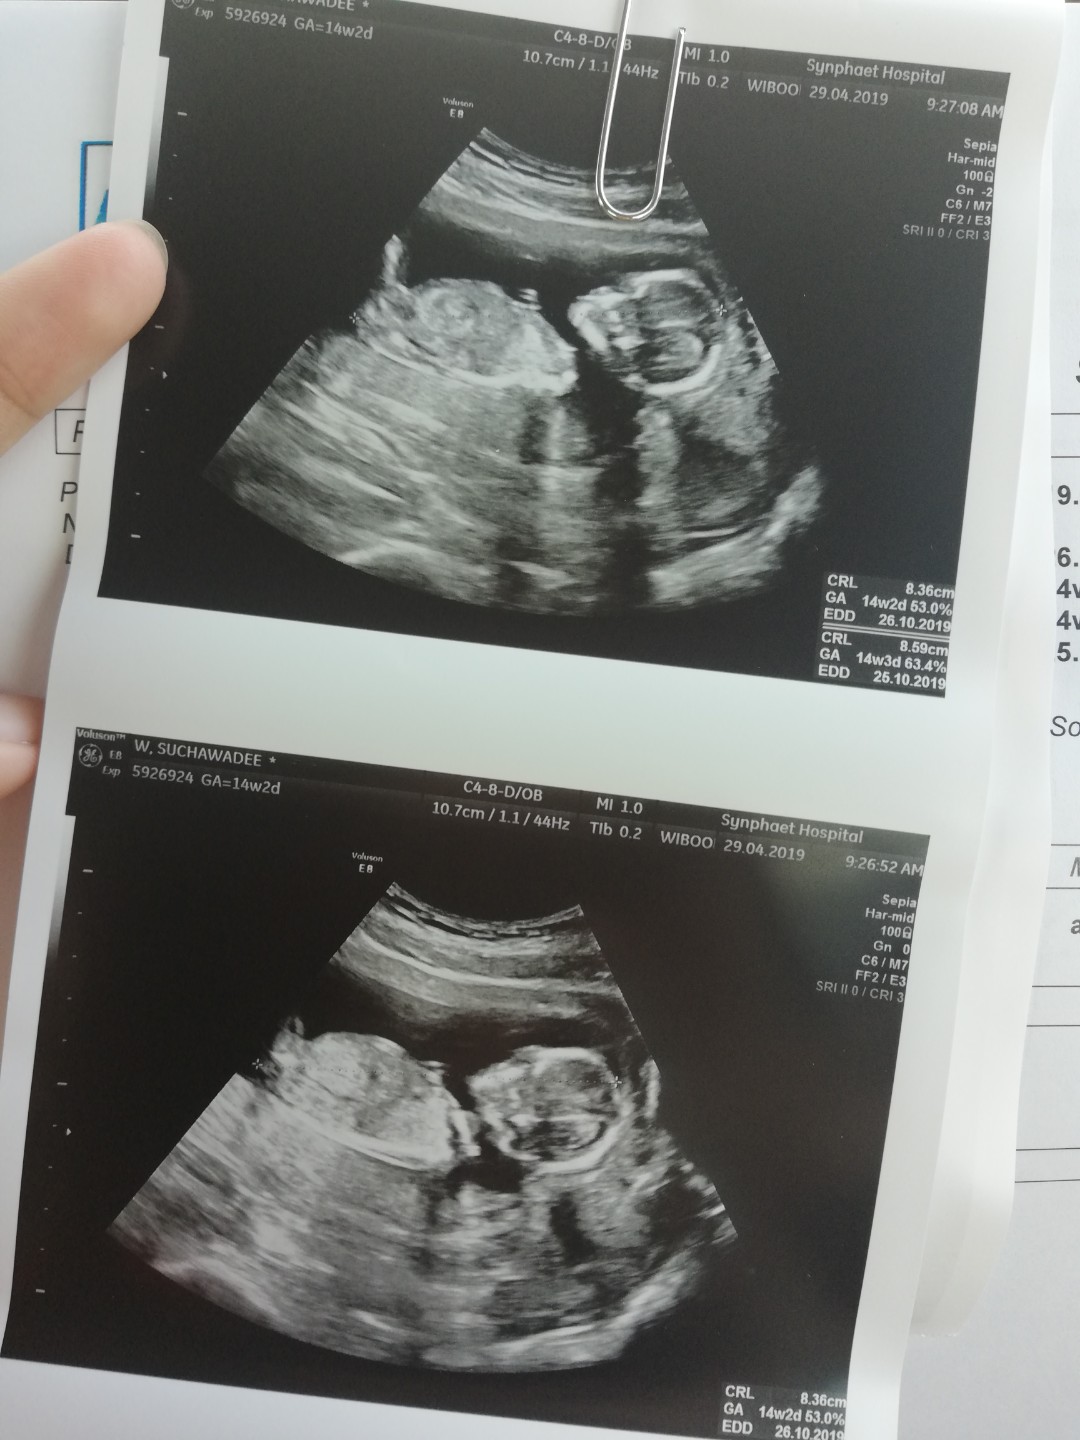

เรามีตอน 14 w ค่ะ